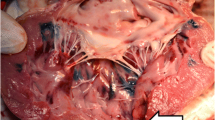

a The variation in cardiac enzyme before and after laser ablation (*P < 0.05, **P < 0.01); b the measured mean diameter and volume of the lesions; c example of the ablation zone, the center black region was charred and surrounded by white coagulated regions; and d pathological examinations of lesions showing the comparison of the ablated regions and the normal myocardial tissue. Asterisk shows the red blood cells infiltrating the widened intercellular space (hematoxylin and eosin ×200)

Gross and pathological examinations

The mean diameter and volume after 5 min ablation are significantly larger than the region ablated for 3 min in Fig. 5b. Figure 5c shows an example of myocardial lesions ablated for 5 min. The charred and coagulated necrotic regions are clearly seen with borders that distinguished these regions from the surrounding normal healthy myocardial tissue. A representative pathological examination of ablated myocardial lesion at ×200 magnification is shown in Fig. 5d. Normal myocytes are distributed evenly (arrow head) with the nuclei showing small dark-blue or purple precipitate. The ablated myocardial tissue (arrow head) is contracted, and the cells close to the laser show abnormal morphological characteristics. A zone of vacuoles forms a clear boundary between the ablated and normal tissues, and red blood cells infiltrate the widened intercellular space. Compared to normal tissue, the ultrastructure of the lesion is damaged and sparsely distributes, with fewer nuclei and an increasing number of eosinophils.

The results of pathology and the increase of myocardial enzymes indicated damage to the myocardium. Tissue necrosis was clearly observed and suggested irreversible denaturation of proteins mainly due to thermal injury [25]. Around the ablation crater, visible whitening of irradiated tissue was observed, thereby indicating thermal coagulation as shown in Fig. 5c [26]. The pathological figure in Fig. 5d showed a zone of vacuoles lying beneath fragments of carbon in all lesions. Compared with other thermal ablation approaches, the laser required a longer time to create lesions. For example, the insonation time lasted a few seconds when HIFU ablation was performed at an output power of 2000–3000 W [15]. Trans-arterial argon laser myoplasty (wavelength 454–514 nm, power 2–2.2 W, exposure time 12–20 min, total energy 1440–2640 J) was reported, and the in vivo ablated region [27] was comparable with that observed in this study. In our study, the 1-W power Nd:YAG laser achieved the desired ablated region in a relatively short time (3–5 min) with a low intraoperative stimulus. The thickness of the canine septum was approximately 6 mm. Low-power laser instead of high power was utilized to obtain a controllable lesion size without rapid perforation [28]. The large charred region caused by high-power laser was expected to reduce the depth of laser penetration and caused possible damage to the optical fiber [29]. Hence, considering operational safety, the laser in this study was shown to be a safe method for in situ cardiac thermal ablation.